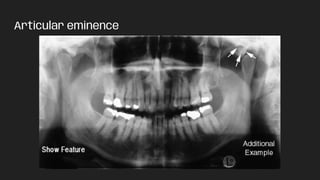

Articular eminence